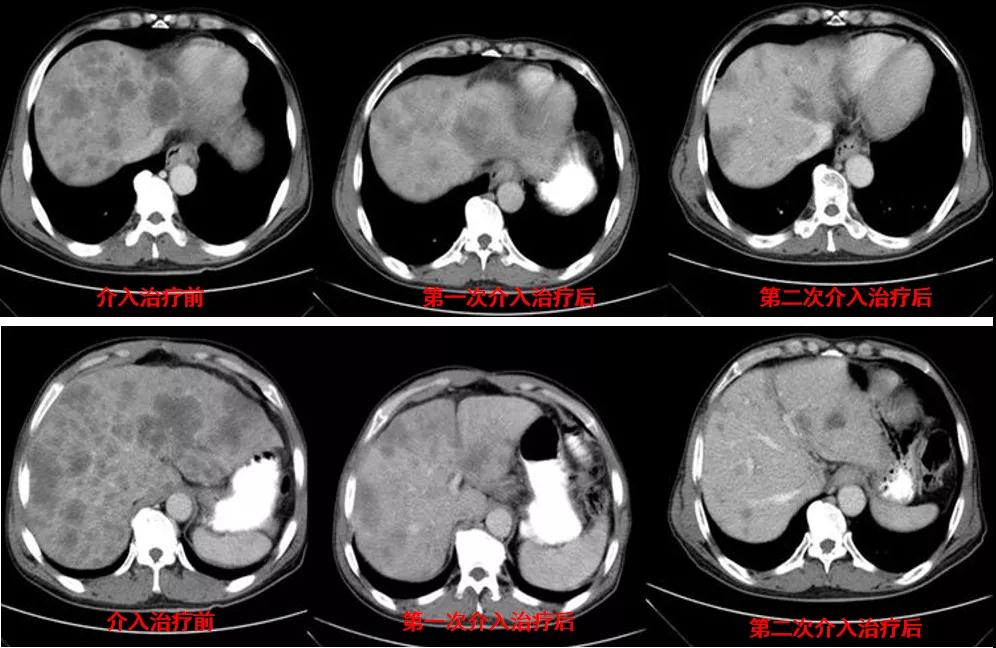

腹部CT检查(2020年11月10日):贲门胃底占位,肝内多发转移灶,腹主动脉旁多发淋巴结肿大,见图1。

图1